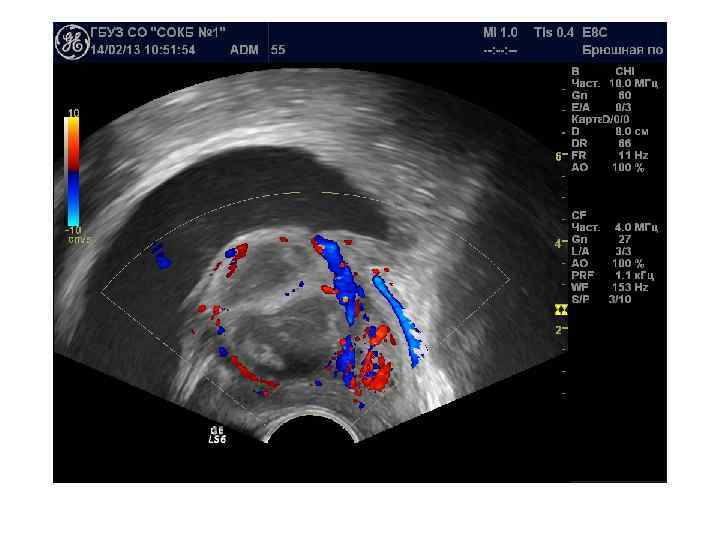

ЦДК и ЭДК опухолевого поражения простаты Большинство авторов отмечает усиление и асимметрию сосудистого рисунка в зоне опухолевого роста.